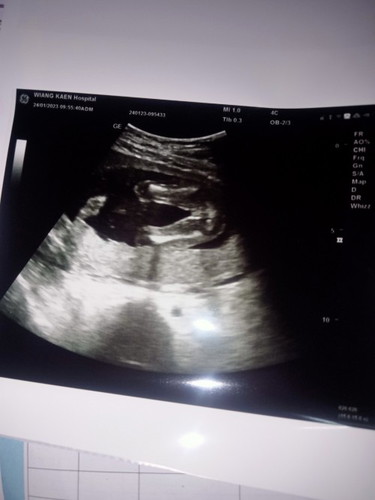

หมอบอกว่าได้ลูกสาวแต่แม่ช่วยดูหน่อยว่าลูกสาวหรือลูกชาย

ของคุณแม่ไม่มีจู๋โผล่ ลูกสาวแน่ๆค่ะ บ้านนี้มีจู๋โผล่มาทักทาย 😆😆😆

ชัดนะคะแม่ ว่าไม่มีจู๋โผล่นั่นแสดงว่า หญิงคะ

บ้านนี้ตอนซาวด์ก็ท่านี้ค่ะหมอบอกได้ลูกสาว

ภาพมุมเดียวกับของเราเลย ลูกสาวค่าา :)

คิดว่าน้องน่าเป็นผู้หญิงค่ะแม่

ลูกสาวนะค่ะแม่ อ้าโชว์มาเลยลูก

เหมือนกันค่ะแม่ ผู้หญิงจ้า

ผู้หญิงอีกเสียงค่ะ